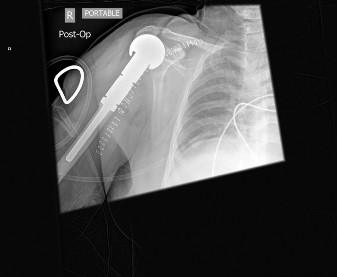

with wide resection and if applicable, reconstruction. Preoperative radiation and/or chemotherapy have no usefulness in treatment of chondrosarcoma. Postoperative x-ray is shown inFigure 8–

- Which of the following complications is seen more commonly in allograft osteoarticular reconstruction than after this type of reconstruction? A. Aseptic loosening

Figure 8–19

Discussion

The correct answer is (B). Allograft reconstructions of the proximal humerus have a higher rate of postoperative fracture than endoprosthetic reconstructions. However, aseptic loosening, abductor dysfunction leading to instability, and proximal migration are all postoperative problems that can be seen with endoprosthetic reconstructions of the humerus. Objectives: Did you learn...?